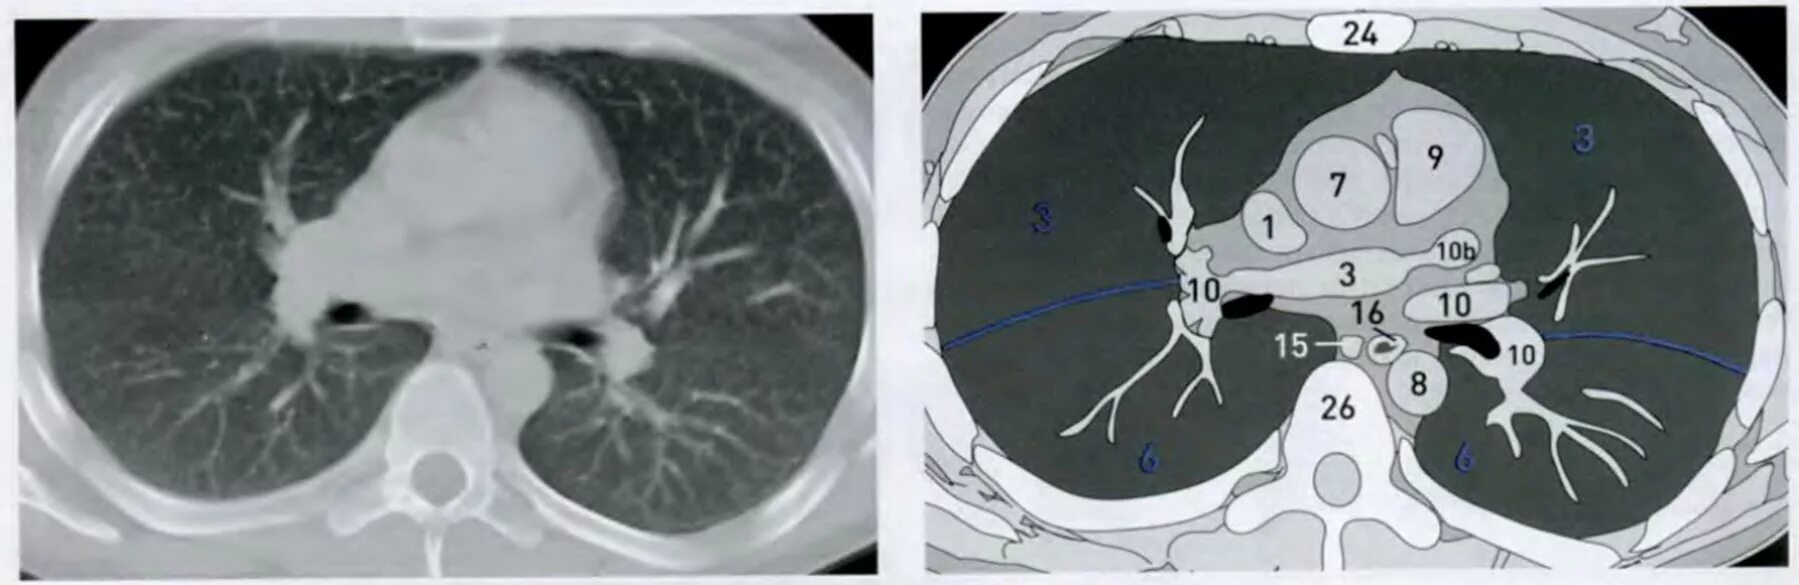

Легочный ствол на кт